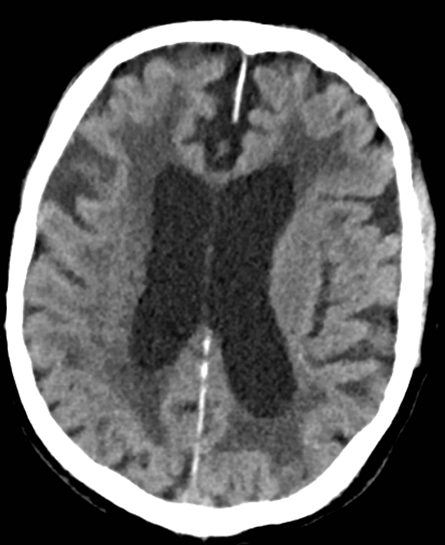

Exvacuo or normal pressure hydrocephalus?

Ex-vacuo hydrocephalus with diffuse cortical atrophy.

Absence of cortical atrophy below